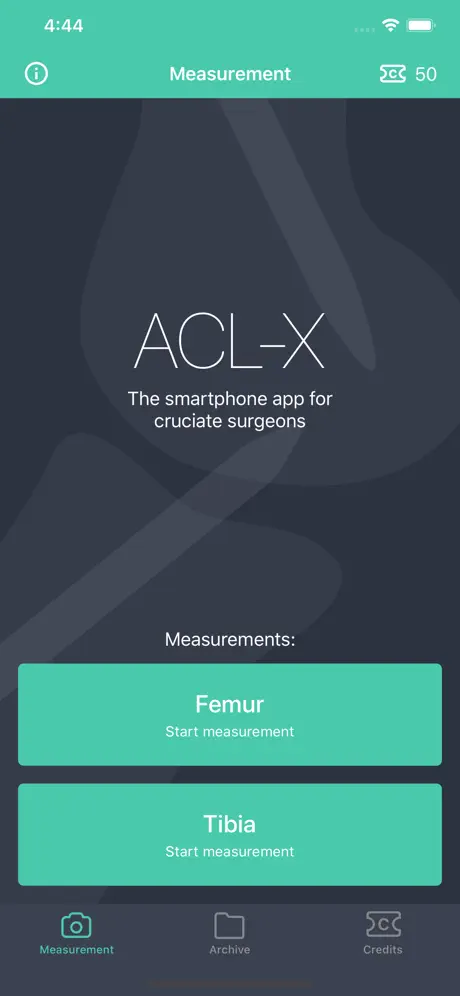

ACL-X

Разработчик:

Linova Software

Описание

ACL-X -- The Smartphone App for ACL Surgery!

This App was developed for knee surgeons performing anterior cruciate ligament (ACL) reconstruction and using intraoperative fluoroscopy to increase precision of bone tunnel placement.

By means of supporting lines that you can overlay virtually over the X-ray photograph in the app, the app can calculate the relative distance of the target point for the k-wire for a femoral or tibial surgery.